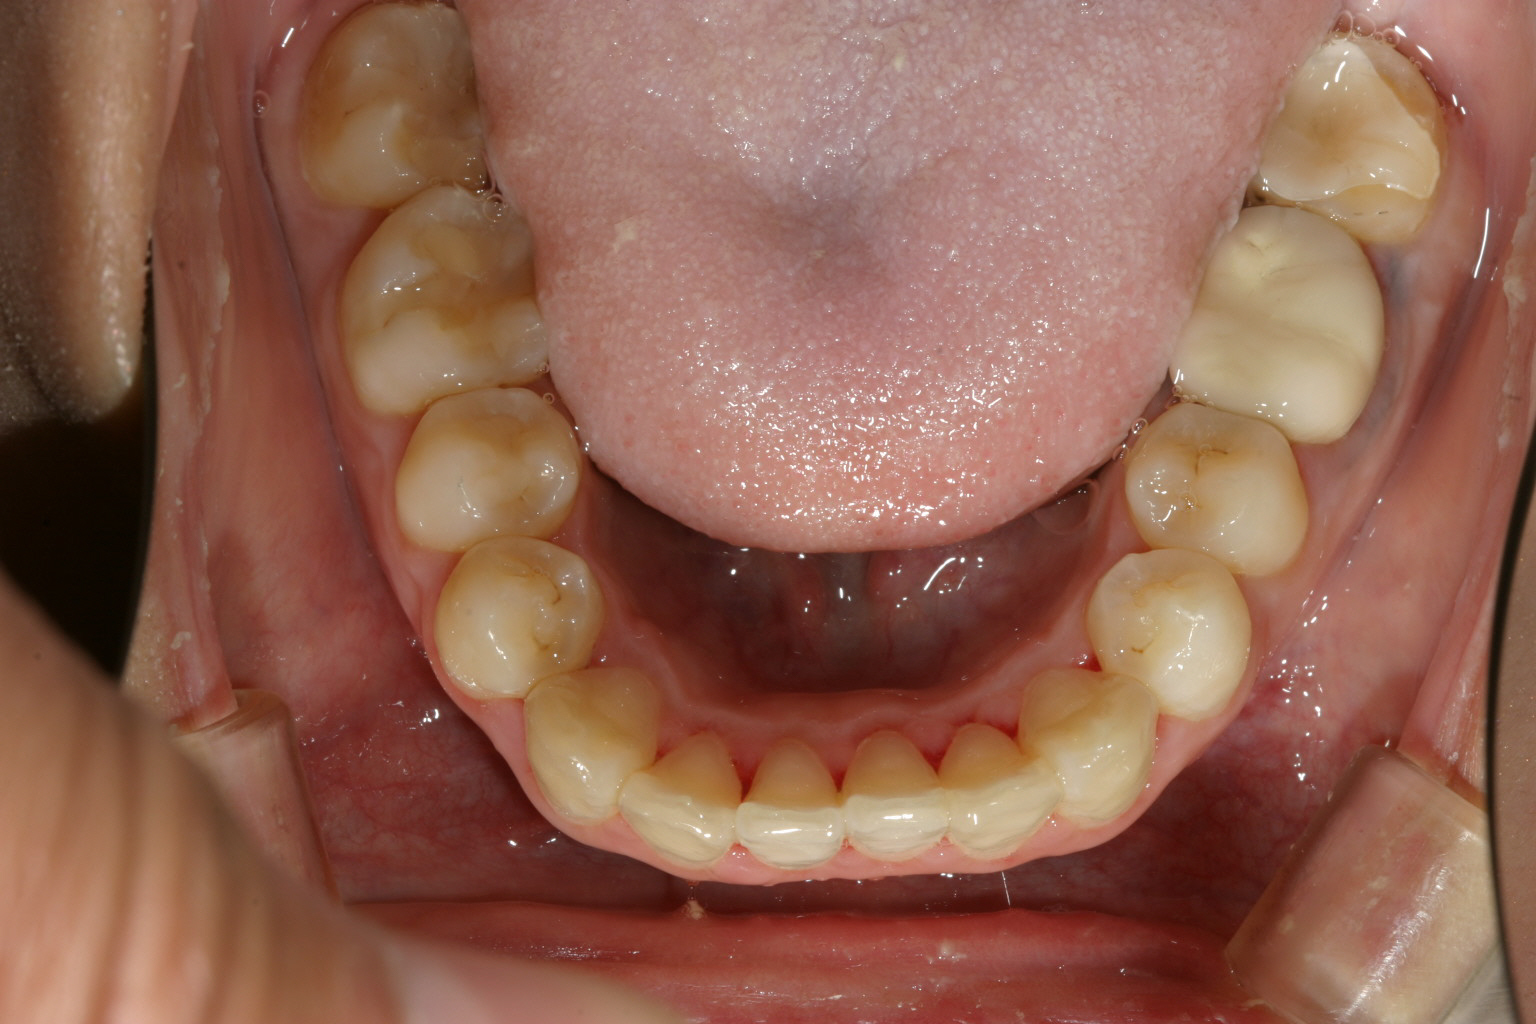

アーチか狭く前歯部が飛び出しています。

下顎もアーチが狭い為その付けが前歯にきて叢生になっています。

上下ともかなり飛び出しています。

アーチを広げ、IPR(歯と歯の隙間を削る)を加え 出っ歯を改善しました。

下顎も上顎と同じ様にアーチ拡大とIPRです。